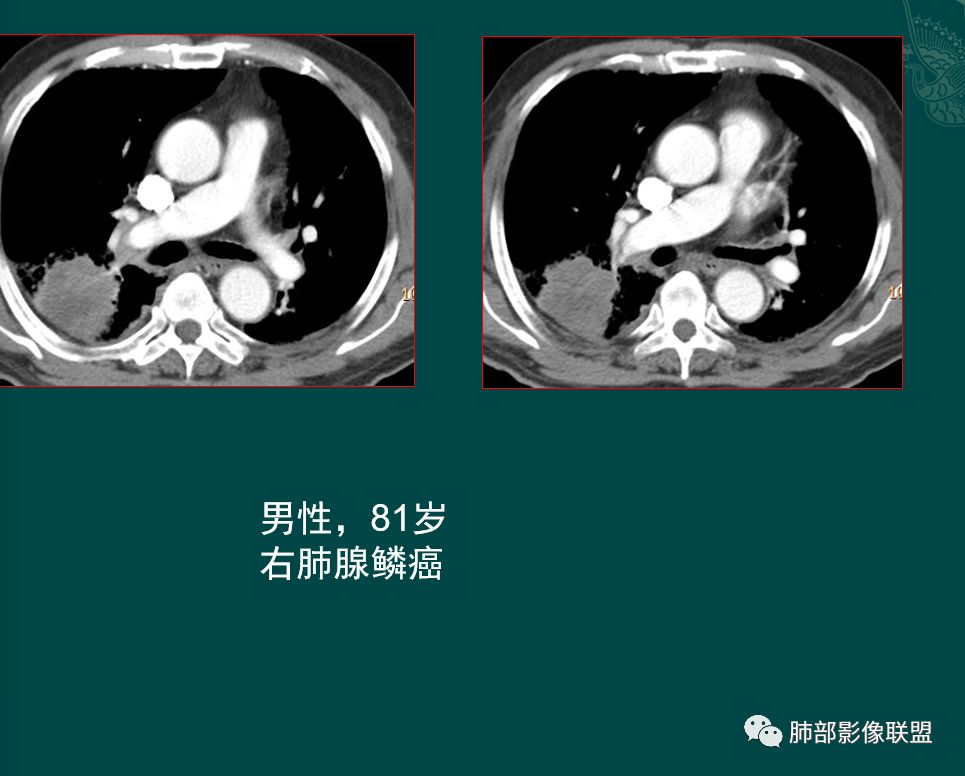

右肺下叶实性结节,肺气肿背景

抗炎治疗后周围渗出减少,结节大小无明显变化

形态呈山丘样改变,边缘膨隆

指状突起

浅分叶

胸膜下脂肪间隙不清

增强后不均匀强化,中心可见边界不清低密度坏死区,沼泽样坏死

右肺下叶实性结节,肺气肿背景,山丘,边缘膨隆、指状突起。治疗前边缘有渗出,治疗后结节边界清晰,大小变化不大。胸膜下脂肪间隙不清,增强后轻度不均匀强化,内部沼泽样坏死。

恶性问题不大,倾向小细胞肺癌。